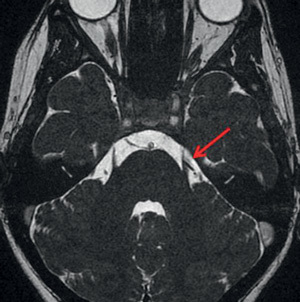

Une patiente de 50 ans présente une névralgie essentielle du trijumeau résistant au ttt médical, on réalise cet examen en vue de la chir, quelle est la séquence? Diagnostic?

Névralgie du trijumeau gauche par conflit vasculo-nerveux;

IRM séquence T2

Déviation de l’émergence du nerf trijumeau gauche par le trajet cisternal de l’artère cérébelleuse moyenne gauche